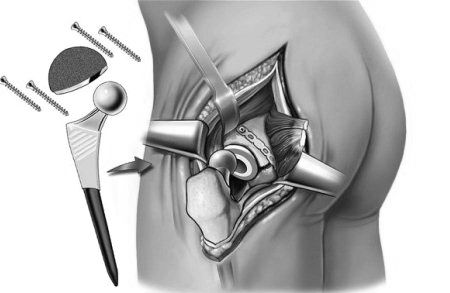

Якщо консервативна терапія не приносить результатів, вдаються до ендопротезування

Заміна (протезування) суглоба при важких формах артрозу

Ендопротезування зруйнованого суглоба дозволяє повністю відновити функцію суглоба і позбутися від болю. В даний час дана маніпуляція є рутинною, існують сотні моделей і десятки виробників різних ендопротезів. Найбільшою популярністю користується операція по заміні великих суглобів нижніх кінцівок. Вже на другий день після заміни, наприклад, тазостегнового суглоба - хворі можуть самостійно ходити.

Застосування ендопротезів збільшує виживаність пацієнтів, оскільки дозволяє їм нормально рухатися. Це важливо для перебігу всіх процесів в організмі, особливо у літніх пацієнтів. Потрібно пам'ятати, що протезування суглоба - відмінна альтернатива інвалідності, проте є найостаннішим аргументом у питанні лікування артрозу.